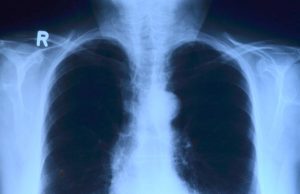

Most Doctors Believe Vaping Causes COPD But Science Shows Otherwise

In what is a clear example of the misinformation circulating about vapes, the global survey found a total of 74% of the participants “incorrectly...

Vaping individuals who don't smoke cigarettes or marijuana, were more likely to report suffering from asthma-like symptoms, than non-vapers, said the researchers. Lead study...

The Danish study titled, “An RCT of acute health effects in COPD-patients after passive vape exposure from e-cigarettes,” looked into the effects of short-term...